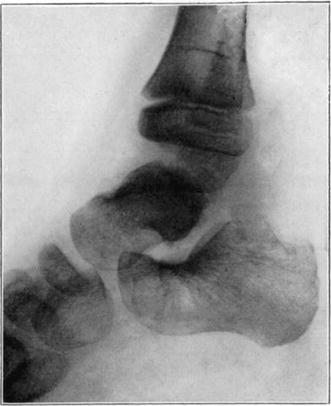

Necrosis of Os Calcis

In fracture of the neck of the os calcis the body may rarely have so much of its blood supply cut off that it undergoes extensive necrosis. Its subsequent history is analagous to that of a necrotic proximal fragment in intracapsular fracture of the neck of the femur. If bony union between the fragments follows, the necrotic body will be invaded gradually by blood vessels, fibrous, osteogenic, and myelogenous tissue, and a gradual replacement of the necrotic by living elements will be brought about. The replacement may be incomplete and the necrotic portion located farthest from the fracture may be broken down by weight-bearing before the ingrowing tissue reaches it, thereby leading to deformity and permanent derangement of the bone.

The following cases are illustrative of this condition.

Case 2. Seventy-four days after fracture of neck of astragalus, posterior dislocation of body, and reduction by operation. Body necrotic and retained normal density. Atrophy of disuse of other bones. Bony union of fracture.

Case 2. One hundred and sixty days after fracture. Body slightly reduced in density near fracture due to invasion from neck.

Case 3. Fresh fracture of neck of astragalus and chip off superior and posterior portion of os calcis.

Case 3. Two hundred and seventy-four days after injury. Fracture of astragalus united. Superior and posterior part of body broken down and irregular while remaining portion dense and transformed. Indicative of necrosis of body with secondary changes.

Case 3. Eighteen months after injury, showing a defective but gradually reforming articular portion of the body of the astragalus.

The blood supply of the astragalus is derived mainly from a branch of the arteria dorsalis pedis which traverses the sinus tarsi lateral to the neck and breaks up to enter the bone near the junction of the neck and body along the lateral and inferior surfaces. There are very small branches entering the bone mesially and posteriorly at points of ligamentous and capsular attachments. Apparently when there is a fracture along the junction of body and neck the important vessels to the body are interrupted and there may be insufficient circulation through the remaining vessels, so that aseptic necrosis of a large part or all of the fragment follows. It is evident from the partial collapse which occurred in Case 3 that when necrosis of the body is diagnosed, the limb should be protected from weight-bearing for at least several months,—until union, revascularization, and transformation of necrotic area has been largely brought about. It seems probable that some of the bad results that have been reported in fracture of the neck of the astragalus, either united or ununited, have been due to overlooked aseptic necrosis of the body.